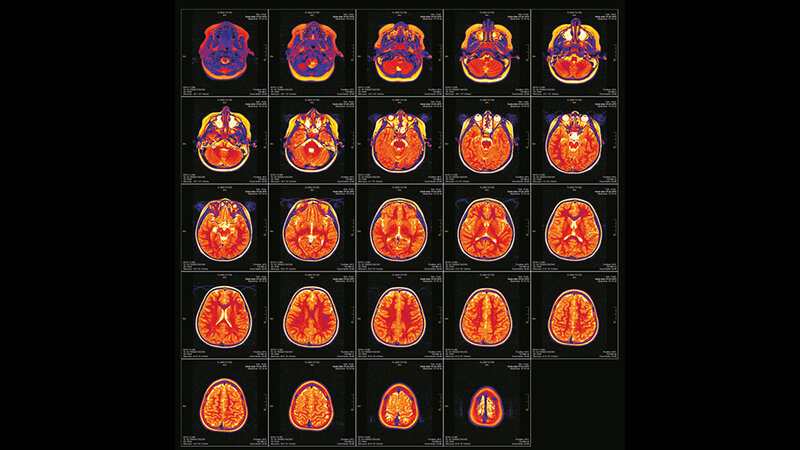

Entnommen aus MTA Dialog 01/2015